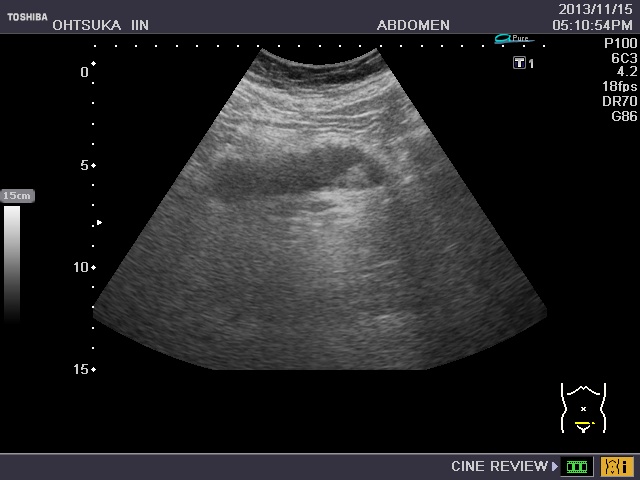

t‘ŸŠà(“–‰@Ç—áE’´‰¹”gŒŸ¸‰æ‘œ)